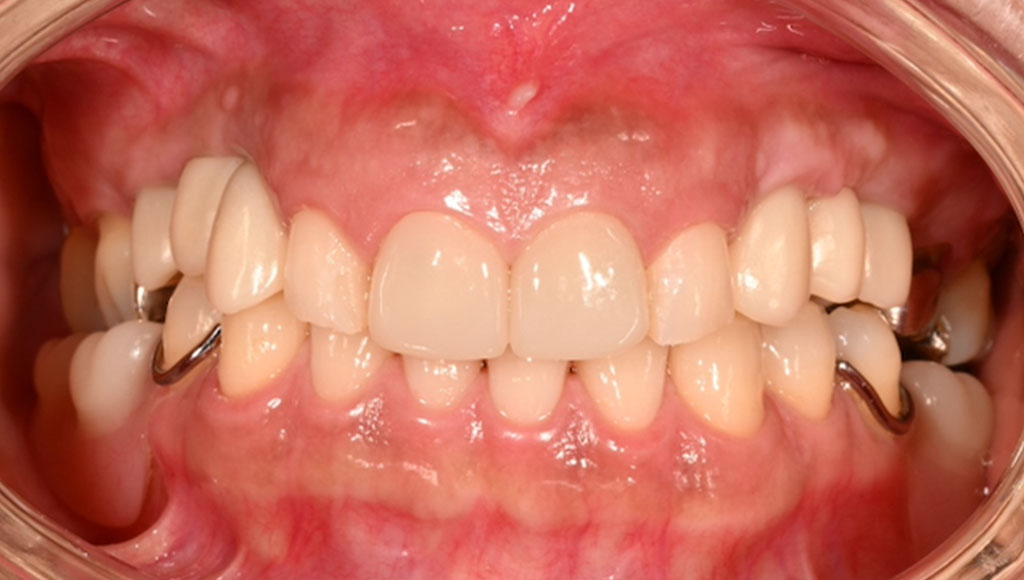

After1

患者様の主訴

40代女性。横浜市在住。左上1番右上1番のクラウンに着色があり審美的に問題を抱えていたため、ご来院されました。

診断結果

ジルコニアクラウンを装着するために元のブリッジを外し、歯の形成を行いジルコニアクラウンをセット

治療内容

ジルコニアクラウンを装着するために元のクラウンを外し、歯の形成を行い光学印象(プライムスキャンによる)型取りを行いました。光学印象のデータを元に当院の院内技工室にてデジタル加工を行い、ジルコニアクラウンを作成し、セットを行いました。

治療期間

2回

治療費用

総額:330,000円(税込)

◼️内訳

ジルコニアクラウン(前歯):150,000円(税込)/1本×2本

光学印象(プライムスキャン)

リスク・副作用

補綴物の脱落・欠落、咬合違和感、色調補正